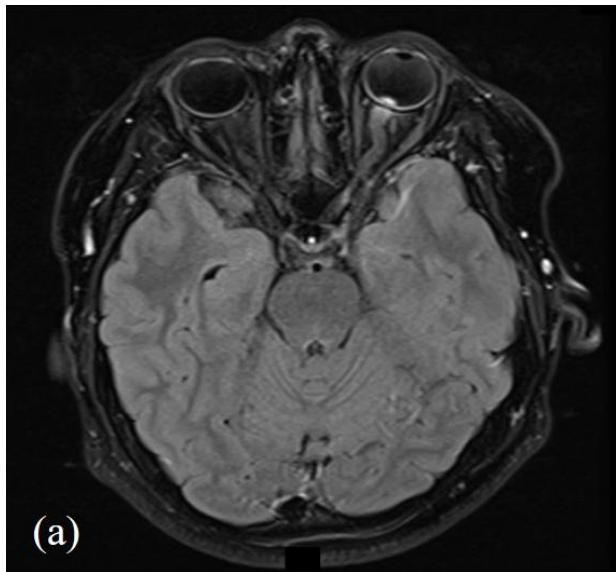

The patient's infectious screen was negative. This included; Quantiferon-TB Gold, Syphilis, Bartonella henselae immunoglobulin G (IgG)/immunoglobulin M (IgM), human immunodeficiency virus (HIV) antigen and antibody (Ag/Ab), cytomegalovirus (CMV) IgG/IgM, Toxoplasma IgG/IgM and Leptospiral IgM enzyme-linked immunosorbent assay (ELA). Serum angiotensin converting enzyme (ACE) and chest x-ray were normal. Lyme disease serology (Borrelia burgdorferi) was not tested as he had not travelled outside of NZ. Bartonella henselae serology was negative when sequentially tested on initial presentation as well as 4 and 8 weeks later. He had a normal full blood count, liver function, renal function, serum folate and B12. His antinuclear antibodies (ANA) were weakly positive and inconclusive with negative extractable nuclear antigen (ENA), antineutrophil cytoplasmic antibodies (ANCA) and double-stranded deoxyribonucleic acid 40 (dsDNA). Neuromyelitis optica (NMO) IgG antibodies were initially positive however negative on repeat testing 4 weeks

later including negative myelin oligodendrocyte glycoprotein (MOG) antibodies. Magnetic resonance imaging (MRI) of the head, orbits and spine with gadovist contrast were consistent with left retrobulbar optic neuritis without intracranial or spinal involvement (figure 3).

Figure 3: MRI head and orbits with (a); T2 axial TSE FLAIR sequence and (b); T1 coronal TSE Dixon sequence with contrast. Focal enhancement of the anterior margin of the left optic nerve at its junction with the globe is demonstrated without other demyelination or parenchymal intracranial pathology.